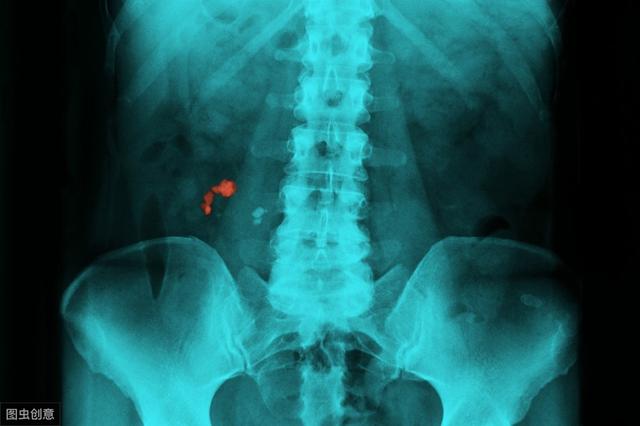

尿路结石也会偷走我们的肾脏。 尿结石大家都不陌生。很多人都知道结石会引起肾绞痛,却不知道结石也会偷走你的肾。

当肾结石随尿液进入输尿管,造成同侧输尿管梗阻,急性完全梗阻,疼痛难忍时,经常就诊。而慢性不完全梗阻的症状不是很明显,慢慢引起肾积水,肾皮质萎缩。久而久之,我们的肾脏会越来越薄,最后只剩下一层皮。

所以当你知道有结石的时候,一定要尽快治疗。不要因为不疼不痒就停止治疗。当结石“偷走”你的肾脏时,剩下的只有遗憾。

尿路结石会导致肾脏萎缩。